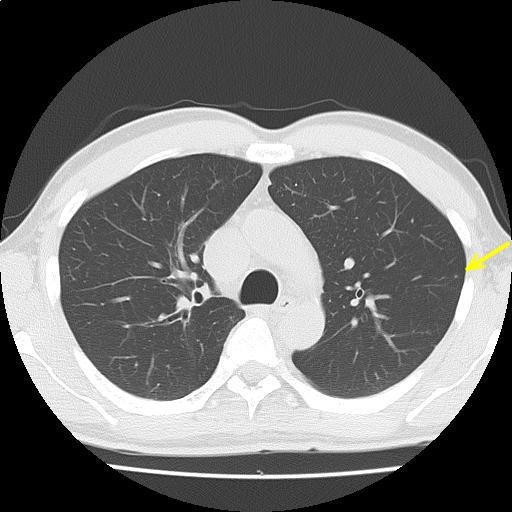

CTスライス画像

(Findings)

両肺末梢に微小結節を散見し、陳旧性炎症性変化と考える。

縦隔リンパ節腫大を認めない。胸水を認めない。